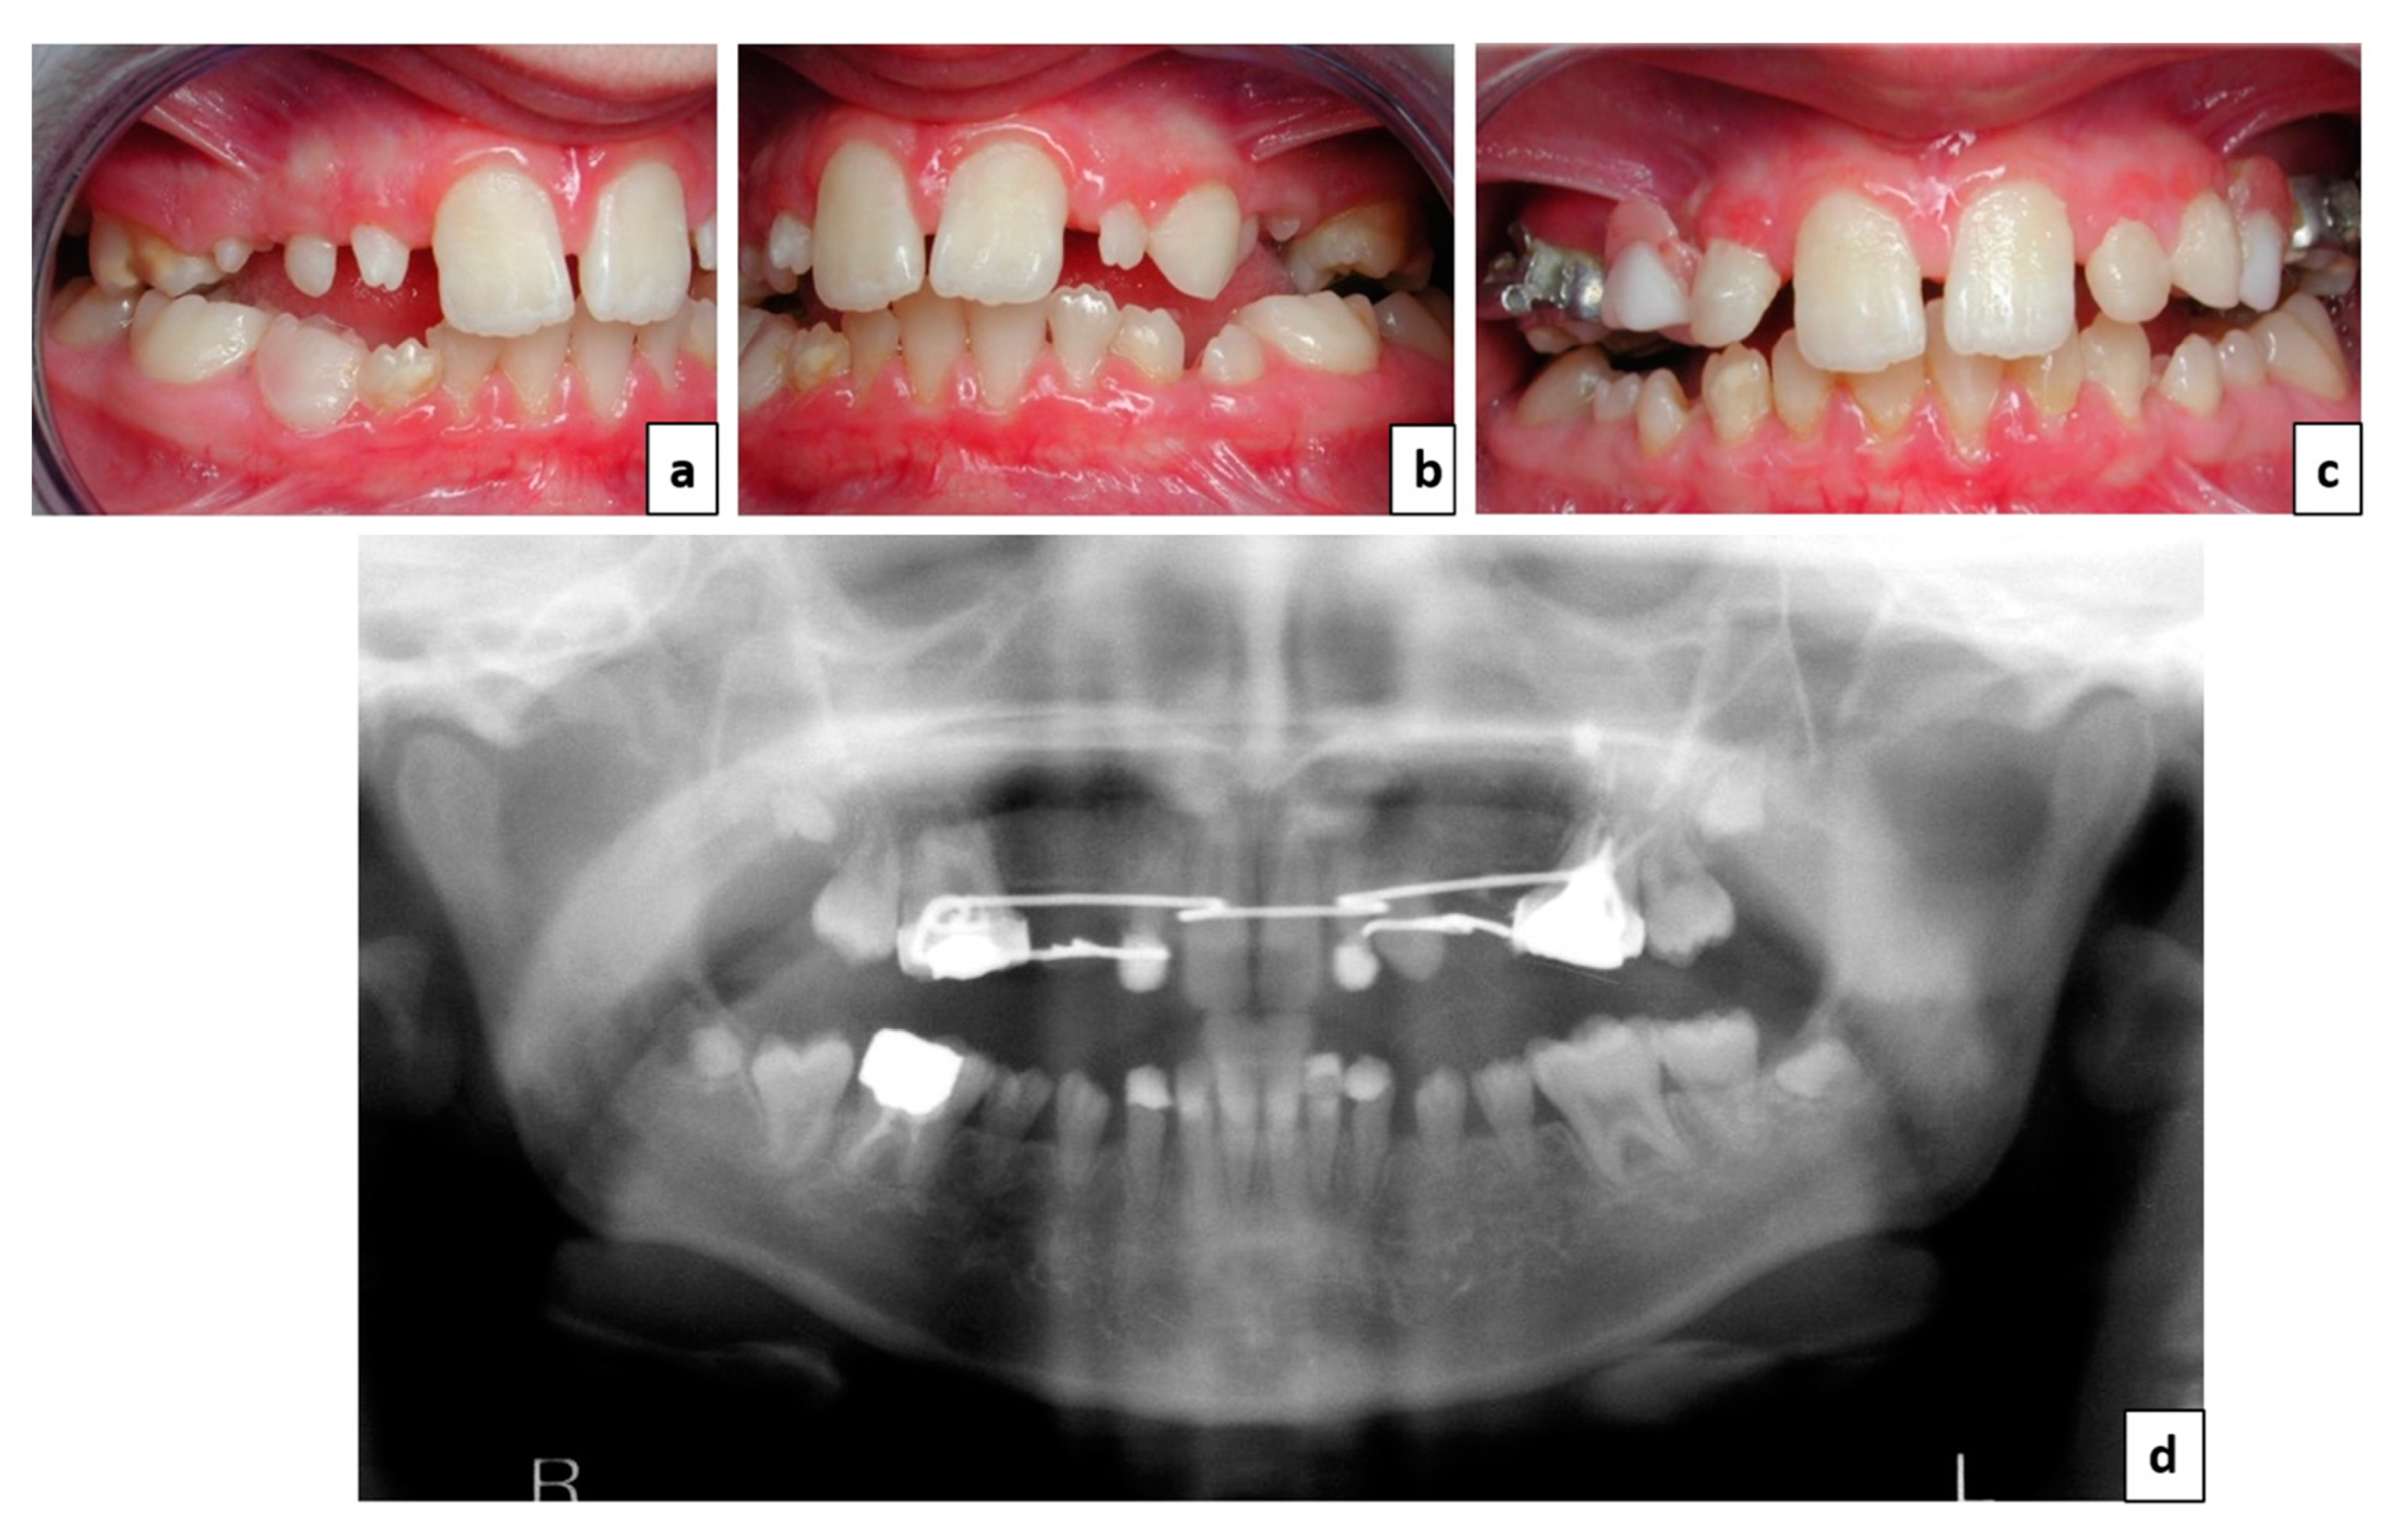

2. Case Report

3. Treatment Plan

4. Therapeutic Management